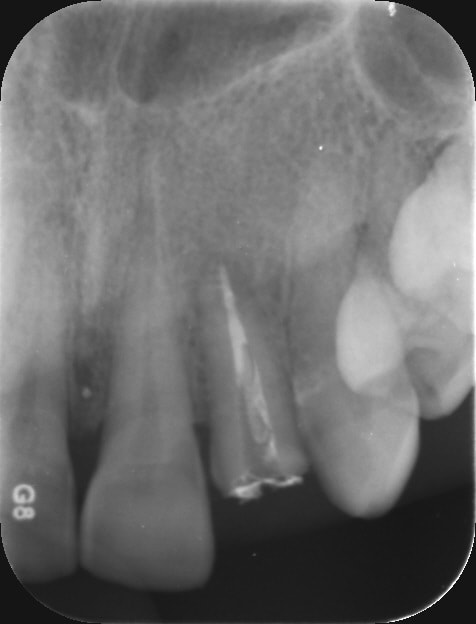

pulpite 16 ; 4 canaux tres difficiles dixit cbct

20 minutes pour trouver les 4 entrées (même la palatine était très difficile)

et paf un S1 gold dans le 2eMV (un tout neuf pour ce canal)

PS : pas de digue parce que sinon tu trouves rien (même la chambre pulpaire a été difficile à determiner )

Pas sur de moi, lachmar, mais tu as peut etre un hiatus entre l'axe de ton bout d'instrument et l'axe de départ. Peut etre que le bon trajet est matérialisé par le tracé vert. J'ai agrandi un peu.

Fauxcanalavoir djnawh - Eugenol

Fauxcanalavoir0 yszo1r - Eugenol